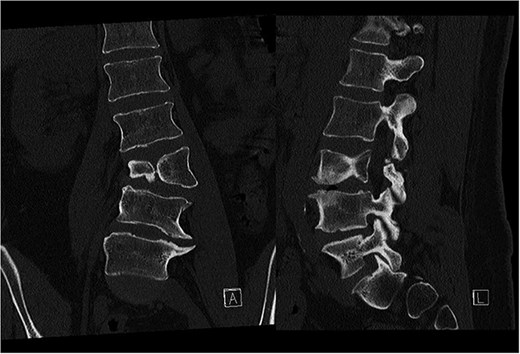

Preoperative CT demonstrating L3 hemivertebra; anteroposterior view (A) on the left side of the image, and lateral view (L) on the right side of the image.

A 24-year-old female with congenital scoliosis caused by a semi-segmented hemivertebra at L3 (Figs 4 and 5) was under follow-up at our institution for chronic back pain and left leg pain, without motor deficits. She had been referred to our institution three years earlier, at which time surgical resection was indicated. However, the procedure was postponed due to patient's personal reasons.

CT-based 3D reconstruction revealed a semi-segmented hemivertebra at L3, resulting in a 32° Cobb angle of congenital scoliosis (Fig. 4). We decided to perform hemivertebra resection, L3 laminectomy, L2-L4 fixation with L3–4 cage fusion, and scoliosis correction. CT-based resection was 3D planned using EBS software (Fig. 6). Fixation from L2 to L4 was achieved using pedicle screws under fluoroscopic guidance, followed by L3 laminectomy. After accessing the L3–L4 disc space, a 3D real-time EMN-guided total resection of the L3 hemivertebra was performed (Fig. 6), and a cage with autogenous bone graft was inserted at the L3–L4 level. The left-sided L3 nerve was found to have an accessory branch, which was successfully preserved. Scoliosis was corrected using standard deformity correction maneuvers.